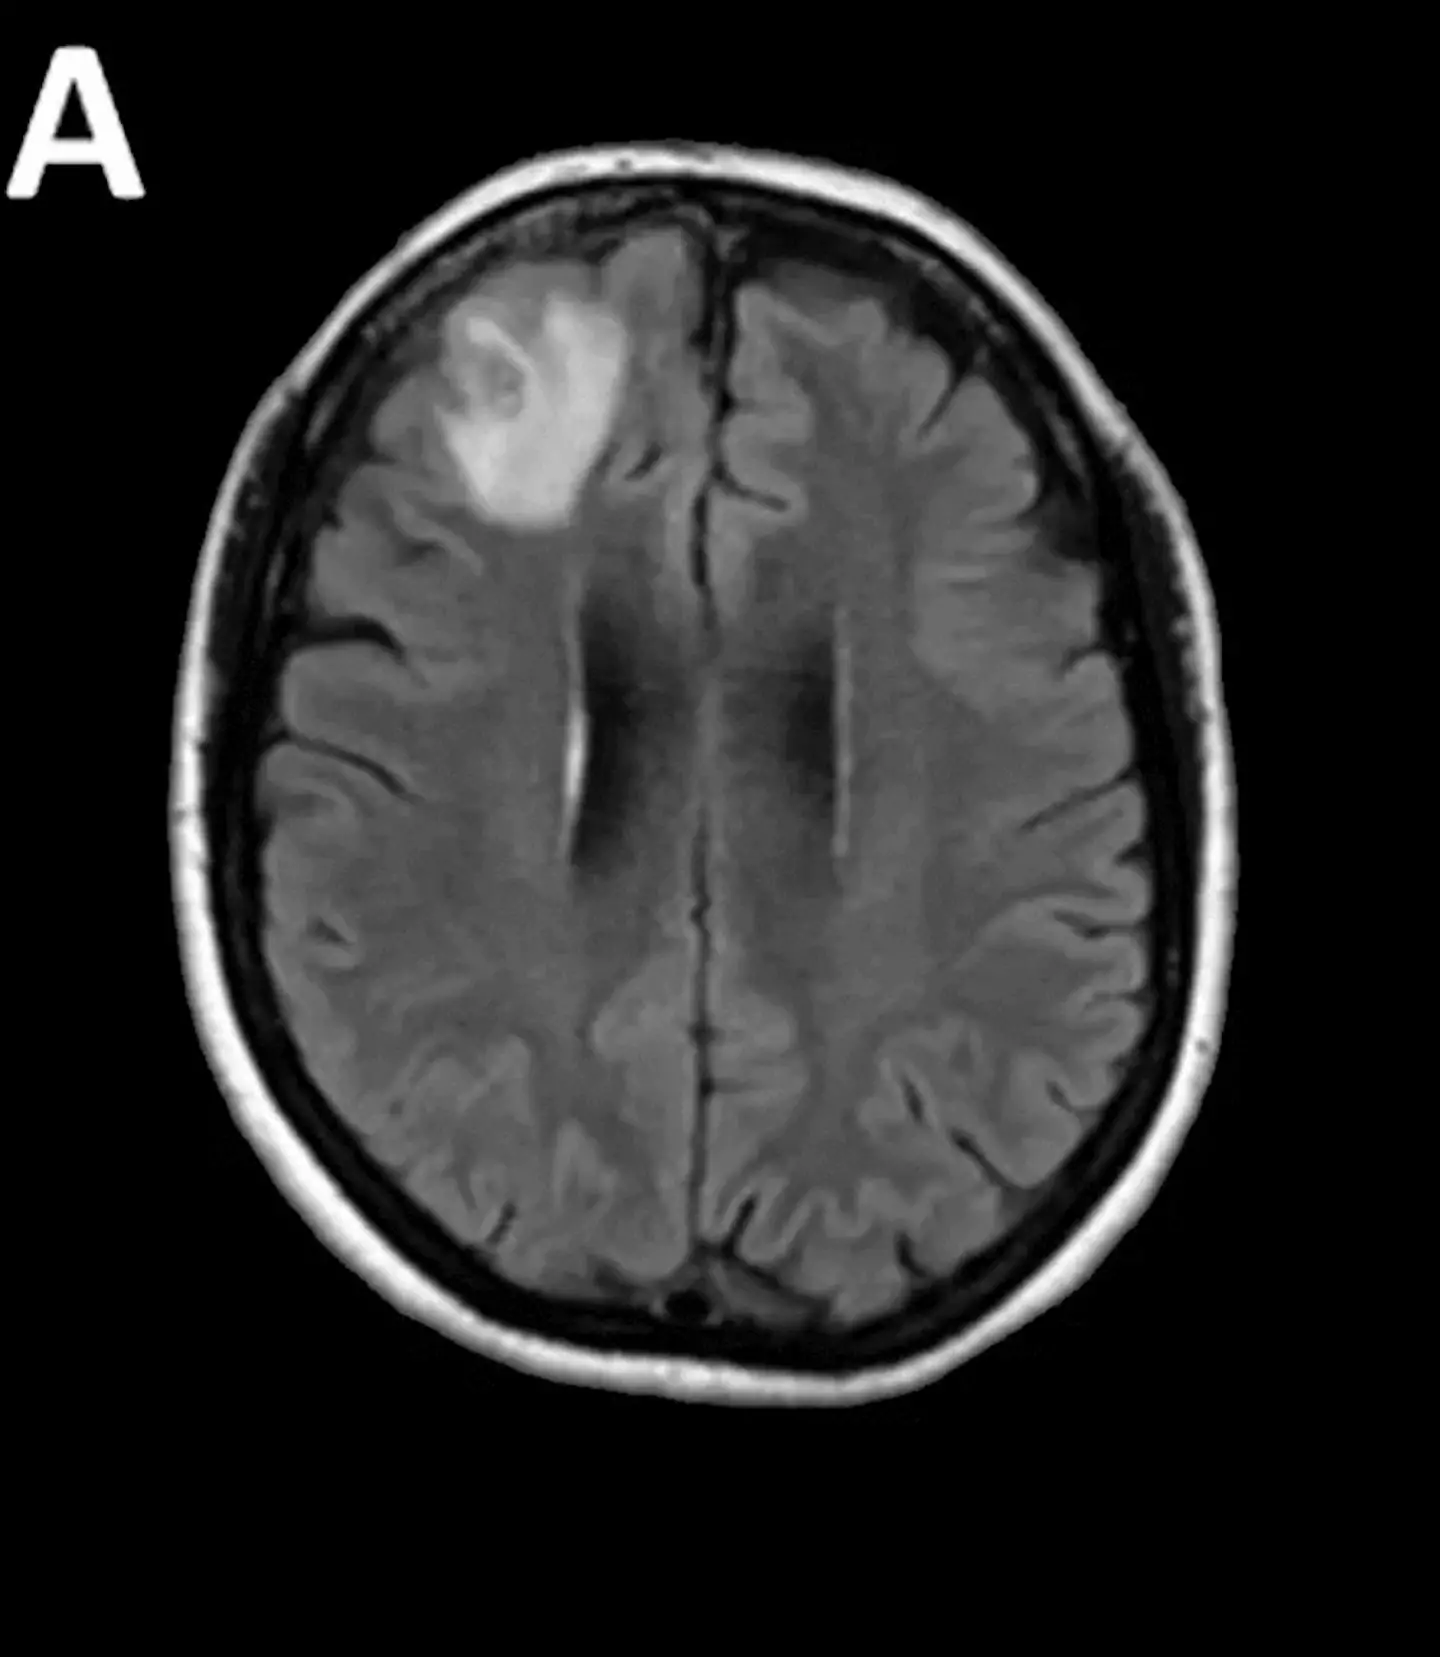

Scans would also reveal changes in the 64-year-old’s brain and fearing the worst, medics did a brain biopsy.